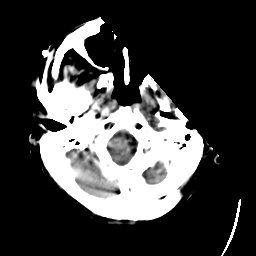

Meningioma: Roentgen-ray CT #1 -- Slice #0

[Home][Help][Clinical] Slice 0